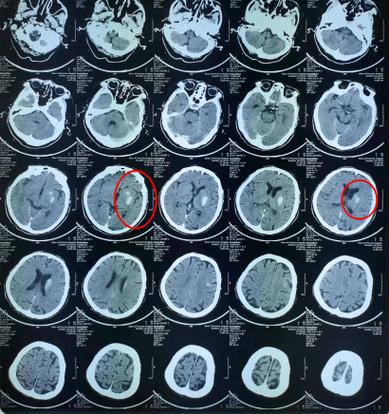

这份报告包含了三个关键信息点:检查方法(脑CT)、病变位置(基底节左侧)、病变性质(脑梗)。

病变位置:基底节左侧

- 基底节是什么? 您可以把大脑想象成一个复杂的城市,基底节就是这个城市里非常重要的“交通枢纽”和“控制中心”之一,它位于大脑的深部,负责协调运动、控制肌肉张力、以及参与一些高级认知功能。

- 左侧意味着什么? 大脑的左半侧主要控制右侧身体的功能,左侧基底节发生梗塞,通常会导致对侧(即右侧)身体出现症状。

病变性质:脑梗(脑梗死)

- 脑梗是什么? “梗”堵塞”的意思,脑梗,全称是“脑梗死”,也叫“缺血性脑卒中”,通俗地讲,就是给大脑某部分区域供血的血管被堵住了,导致该区域的脑细胞因为缺血缺氧而死亡。